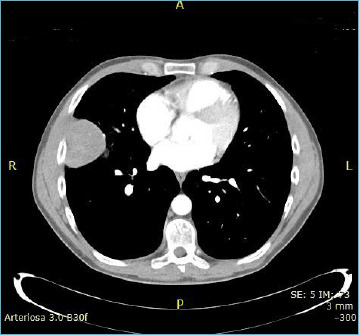

世界卫生组织第五次胸部肿瘤分类将胸部SMARCA4缺失性未分化肿瘤(SMARCA4-UT)列入 "肺部其他上皮性肿瘤 "一章。在此,我们介绍了一例保留 SMARCA4 表达、缺乏 NUT 融合蛋白和 SMARCB1/INI1 表达缺失的胸腔未分化肿瘤。在介绍了该肿瘤的临床和病理特征后,我们对相关文献进行了综述。尽管该肿瘤非常罕见,但我们认为应将其归入胸部未分化肿瘤的异质性组别中。

The 5th WHO classification of thoracic tumours includes thoracic SMARCA4-deficient undifferentiated tumour (SMARCA4-UT) among the "other epithelial tumours of the lung" chapter. Herein, we present a case of undifferentiated thoracic neoplasm with retention of SMARCA4 expression, lack of NUT fusion protein and loss of SMARCB1/INI1 expression. After presenting the clinical and pathological features of the tumour, we carried out a review of the literature on the same topic. Albeit very rare, we believe this entity should be included in the heterogeneous group of undifferentiated neoplasms of the thorax.